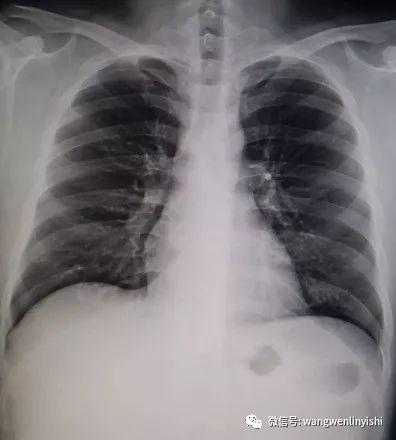

The upper part of the patient’s chest wall is protruded as a whole, coupled with depressions in the central and lower regions, presenting a classic example of Wenlin chest.

Wenlin chest is a distinctive chest wall deformity that was often mistakenly identified as pectus carinatum in the past. However, unlike PC, which is characterized by a single protrusion, Wenlin chest involves both protrusions and depressions, classifying it as a kind of complex chest wall deformities. This malformation can not be corrected by traditional surgeries that work for PC. Notably, the depression in Wenlin chest is only apparent in comparison to the protrusion of the upper chest wall, without significantly compressing the patient’s heart.